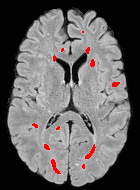

We observed that memberships predicted with an FC layer result in more false positives compared to a fully convolutional network. An example is shown in Fig. 2, where lesion memberships are generated from MPRAGE and FLAIR using the proposed model of convolutional pathways and a comparable model where the last convolutional pathway after concatenation (see Fig. 1) is replaced with a FC layer predicting voxel-wise memberships. The membership image generated with an FC layer, although being close to inside the lesions, has high values () in the left and right frontal cortex where the FLAIR image shows some artifacts. However, the membership obtained with the proposed method shows relatively low values near the frontal cortex.

With FC layer, voxel-wise predictions are performed for each voxel on a new image. Therefore the prediction time for the whole image comprising millions of voxels can take some time even on a GPU, as mentioned in Wachinger et al. (2017). In contrast, with fully convolutional prediction, lesion membership estimation of a mm3 MR volume of size takes only a couple of seconds. Note that although patches are used for training, the final trained model contains only convolution filters and does not depend in any way on the input patch size. Therefore during testing, the lesion membership of a whole 2D slice, irrespective of the slice size, is predicted at a time by applying convolutions on the whole slice. Without an FC layer, the images need not be decomposed into sub-regions, e.g., Kamnitsas et al. (2017). Consequently, there is no need to employ membership smoothing between sub-regions. In addition, since the training memberships, generated by Gaussian blurring of hard segmentations, are smooth, the resultant predicted memberships are also smooth (Fig. 2 last column).